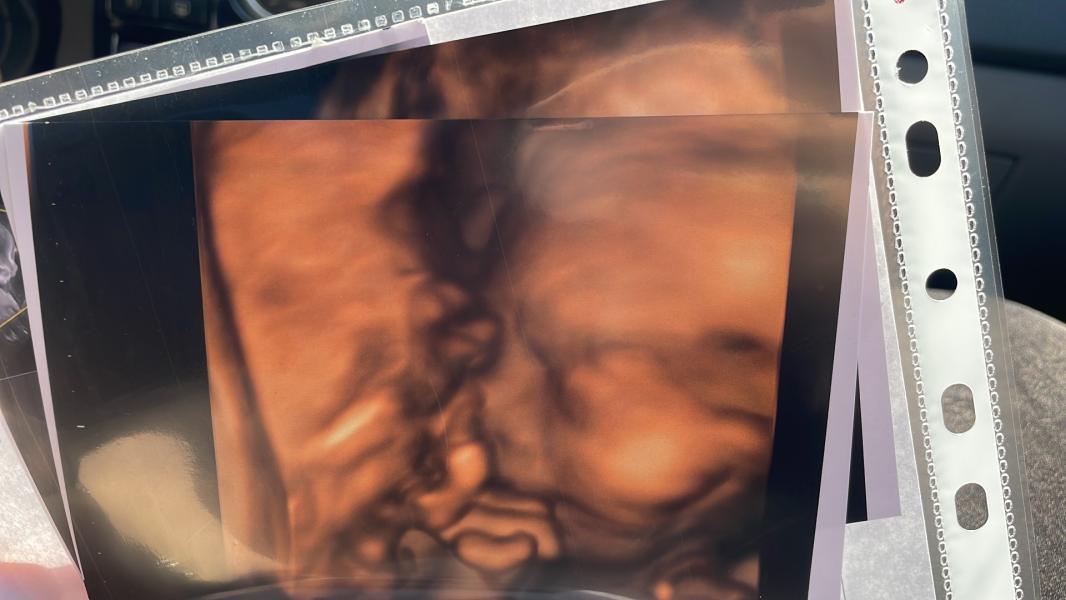

С 1 раза не получилось сделать фоточки(никто, кроме неё не делал мне больше 1-2 фоток), отправила меня поесть сладкого, походить, сделать все свои дела и через 15 мин снова завела, хоть он и упёртый, но что-то да получилось 🤣

Я тоже люблю ее и готова ждать вечно ее . Потому что она относится не только беременной хорошо , но и ребёнку и удовлетворяет все потребности : качественные фото , описание малыша нам прям буквально по пальчикам

@marii111o, малыш капризный, отказывался показывать лицо

И постаралась выбрать фото, где его меньше всего видно 🥹